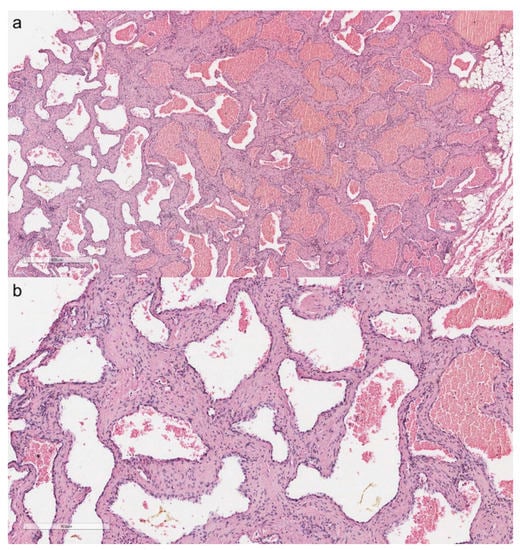

3.4.1. Cavernous Hemangioma of the Thymus

4.4. Soft Tissue Thymic Tumors